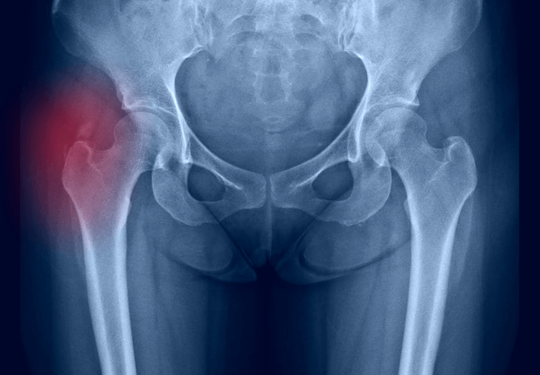

La bursitis trocantérica es una inflamación de la bursa situada en la parte exterior de la cadera, una condición común en atletas y personas que realizan actividades repetitivas. Este artículo explora las causas, síntomas, diagnóstico y tratamiento, incluyendo las infiltraciones ecoguiadas.

Diagnóstico

Historia clínica y examen físico: Evaluación del dolor y movimiento de la cadera.

Ecografía: Para visualizar la inflamación de la bursa.

Resonancia magnética (RM): Para evaluar el tejido blando y descartar otras causas de dolor.